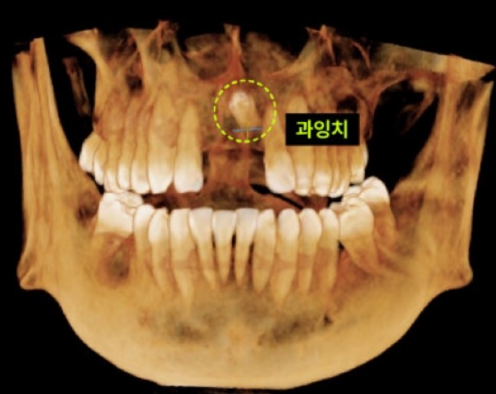

CASE. 30대 남성 환자, "앞니 임플란트 하고 싶어요!" 30대 남성 환자분이 앞니 임플란트 시술을 위해 내원하셨지만, CT촬영 결과 예상치 못한 매복 과잉치가 발견되었습니다. 이는 정상 치아 외에 추가로 자란 불필요한 치아로, 발견 즉시 치료하는 것이 중요합니다. 과잉치, 왜 치료해야 할까? 과잉치는 다양한 문제를 일으킬 수 있어 발치가 필요합니다.

이백점치과의 정밀 진단 환자의 과잉치는 입천장 뼈 속에 거꾸로 누워있었고, 중요한 신경과 혈관이 지나는 '비구개관(Incisive Canal)'을 침범한 상태였습니다. 이처럼 민감한 부위의 매복 과잉치를 제거할 때는 비구개신경 손상이나 출혈에 각별히 주의해야 합니다. 이백점치과는 최신 장비를 활용한 정밀 진단으로 이런 디테일까지 놓치지 않습니다.